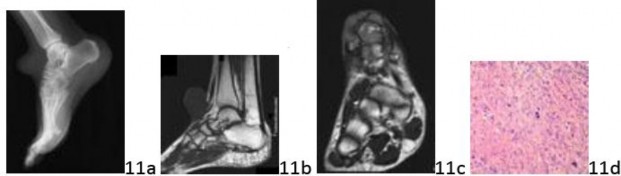

Question 11 A 28-year-old woman has a painless mass on the dorsum of the foot that has been rapidly increasing in size over the last 3 months. It measures 5.7 cm in maximum diameter. A lateral radiograph of the foot is shown in Figure 11a.

Sagittal T1-weighted and coronal T2-weighted MRI scans are shown in Figures 11b and 11c. A photomicrograph from the biopsy specimen is shown in Figure 11d. The most appropriate surgical treatment would likely include which of the following?

Question 11 A 28-year-old woman has a painless mass on the dorsum of the foot that has been rapidly increasing in size over the last 3 months. It measures 5.7 cm in maximum diameter. A lateral radiograph of the foot is shown in Figure 11a.

Sagittal T1-weighted and coronal T2-weighted MRI scans are shown in Figures 11b and 11c. A photomicrograph from the biopsy specimen is shown in Figure 11d. The most appropriate surgical treatment would likely include which of the following?

1. ## Intralesional excision

2. ## Marginal excision and split-thickness skin grafting

3. ## Aspiration and antibiotics

4. ## Wide resection and flap coverage

5. ## Below-knee amputation

DISCUSSION: The clinical presentation, imaging studies, and histology are consistent with a high-grade soft-tissue sarcoma. The MRI scans show a heterogeneous lesion. Histology demonstrates a spindle cell lesion with pleomorphism, atypica, and large bizarre mitoses. Treatment of soft-tissue sarcomas should include at least a wide resection. Intralesional or marginal excision is not advised for high-grade sarcoma. Below-knee amputation is an option for this patient, but most likely limb-sparing procedures for this particular sarcoma would be possible and also more functional while also allowing proper oncologic surgical resection. On this area of the dorsum of the foot, split-thickness skin grafting would likely have a higher failure rate than a fasciocutaneous flap over the tendons. Whereas aspiration of a fluid-containing cystic lesion (ganglion cyst) would be appropriate, it is not appropriate for this solid, heterogeneous lesion. The Preferred Response to Question # 11 is 4.